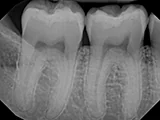

| X-Ray Example |

X-ray taken with the Dexis Sensor |

Dental X-Ray Comparison

X-ray taken with the Caresream® sensorDexis

X-ray taken with the Dexis™ sensorSchick